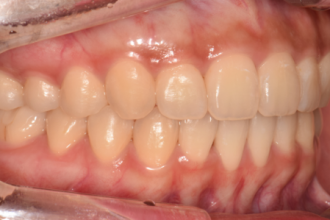

치아교정

굿프렌즈 치과 임상 케이스

직접 확인해보세요!